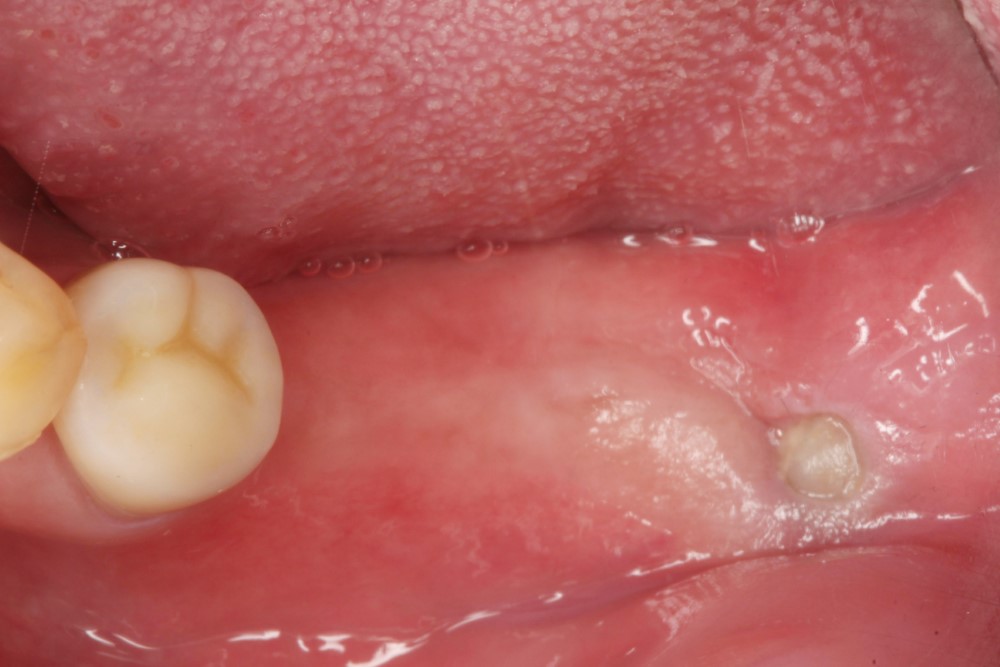

▲數位照片顯示缺牙位置:左下第一大臼齒、左下第二大臼齒